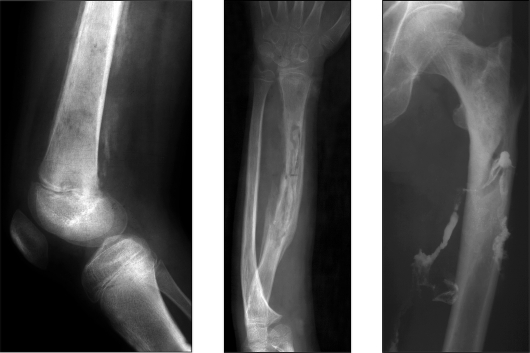

Рентгенологические исследования выделяют четыре варианта течения остеомиелита:

Посттравматический остеомиелит возникает из-за попадания патогенных микроорганизмов в кость открытым путем, например, при контакте с загрязненными предметами или средой. В зависимости от причин, вызвавших заболевание, выделяют следующие виды:

- рентгенография;

Рекомендуется проводить рентгенологическое исследование несколько раз с определенными интервалами. Это важно, так как на ранних стадиях заболевания изменения могут быть не видны на рентгенограммах.